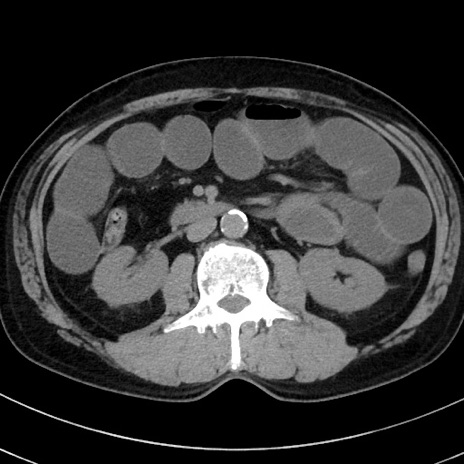

症例38(横断像)

【症例】70歳代 男性

【主訴】腹痛・嘔吐

【現病歴】昨晩より、嘔吐・腹痛あり。今朝になっても嘔吐あり。来院。

【既往歴】心臓バイパス手術、開腹胆摘、腸閉塞

【身体所見】BP 107/71mmHg、HR 116/min、腹部:平坦、軟、下腹部に軽度圧痛あり。反跳痛なし。

【データ】WBC 15100、CRP 0.32